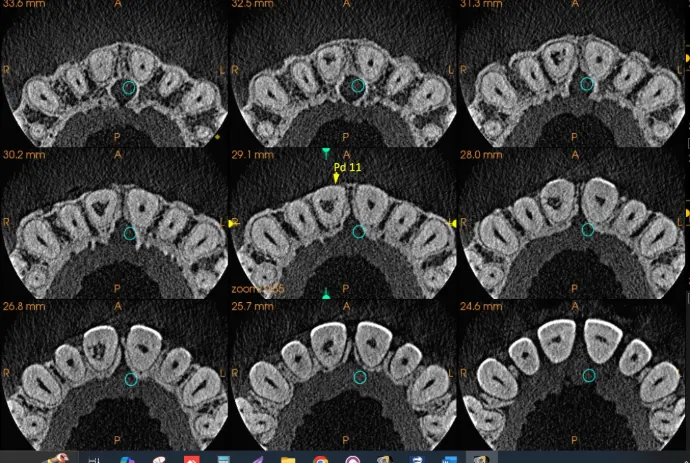

​Como resultados pudimos observar en Pd 11 imagen hipodenso vinculante en zona pulpar interna de dicha pieza dentaria, a posible reabsorción radicular interna. Ver imagen 1,2 Y 3

​No se presentó traumatismo óseo en tabla vestibular ni palatina.